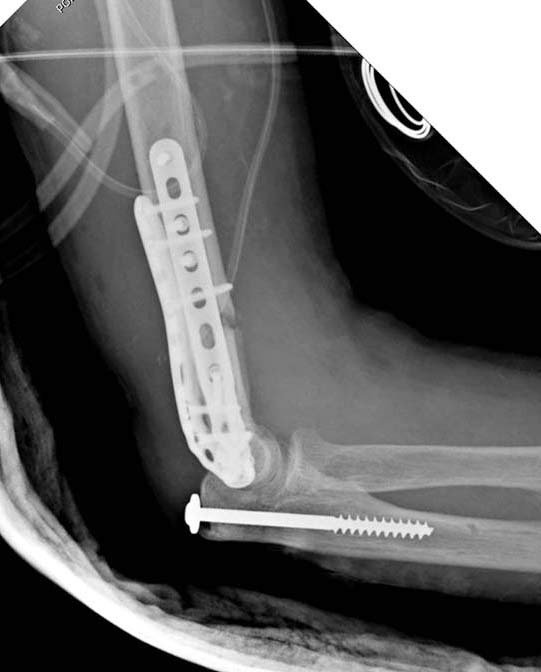

Здесь открытый перелом, временный наружный фиксатор и окончательная фиксация пластинами. Второй случай фиксация без остеотомии отростка пластинами Biomet-DePuy...